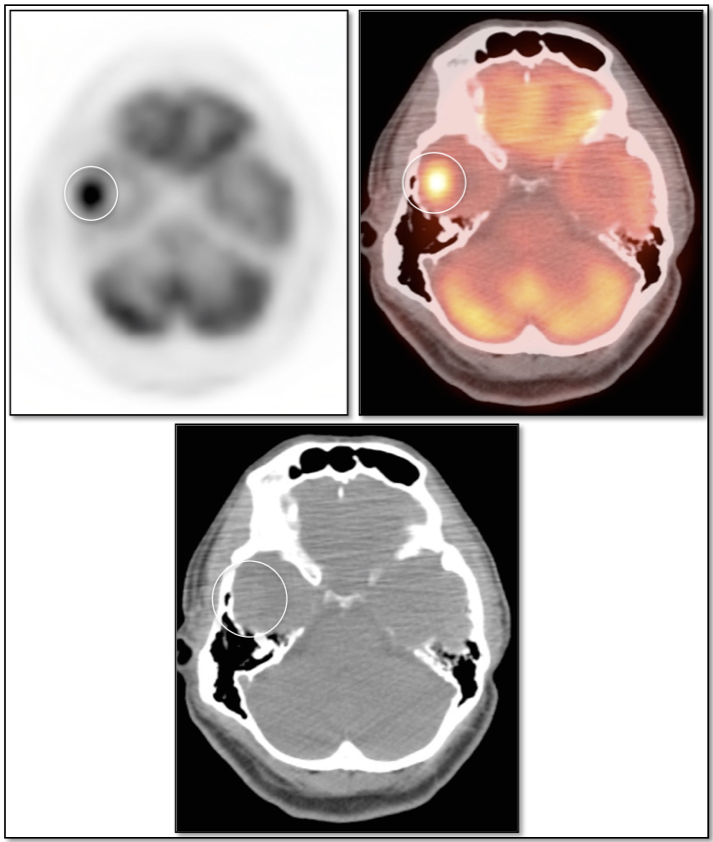

Radiation Necrosis (or Chemonecrosis):

- Necrosis presents months to years after radiation therapy (rarely < 3 months post radiation).

- Difficult to differentiate necrosis from malignancy on MRI, as both demonstrate enhancement.

- Necrosis is typically non-avid on PET images.

- Recurrent malignancy will demonstrate FDG uptake, often focal and involving only a small portion of a surgical cavity. The uptake may be intense (an easy diagnosis) or may be minimally above adjacent background uptake (a more difficult diagnosis, which may require follow-up).

- FDG-avid recurrence should correspond to the area of enhancement noted on MRI (MRI should be done first, with images available at time of PET/CT interpretation).

- If no evidence of pathologic uptake, we report, “There is no evidence of high-grade tumor recurrence.”